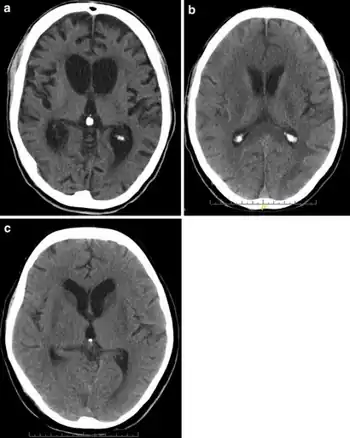

CT scans of hypoxic brain damage individuals a) Brain atrophy and hydrocephalus b)hypodense white matter changes c) bilateral basal ganglia hypodensities

There are several imaging techniques that can aid in diagnosing and assessing the extent of brain damage, such as computed tomography (CT) scan, magnetic resonance imaging (MRI), diffusion tensor imaging (DTI) magnetic resonance spectroscopy (MRS), positron emission tomography (PET), and single-photon emission tomography (SPECT). CT scans and MRI are the two techniques widely used and are most effective. CT scans can show brain bleeds, fractures of the skull, fluid build up in the brain that will lead to increased cranial pressure. MRI is able to better to detect smaller injuries, detect damage within the brain, diffuse axonal injury, injuries to the brainstem, posterior fossa, and subtemporal and subfrontal regions. However, patients with pacemakers, metallic implants, or other metal within their bodies are unable to have an MRI done. Typically the other imaging techniques are not used in a clinical setting because of the cost, lack of availability.[36]